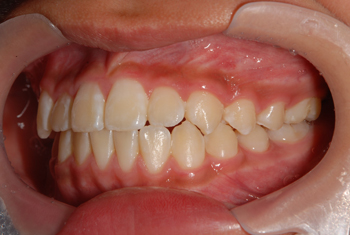

After

反対咬合も治り、歯並びもキレイに揃いました。後は後戻りに注意して、定期検診に来ていただき、大人になっても歯を大切していただきたいと思います。